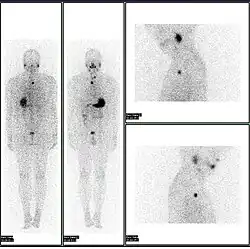

-

A nuclear medicine SPECT liver scan with technetium-99m labeled autologous red blood cells. A focus of high uptake (arrow) in the liver is consistent with a hemangioma. -